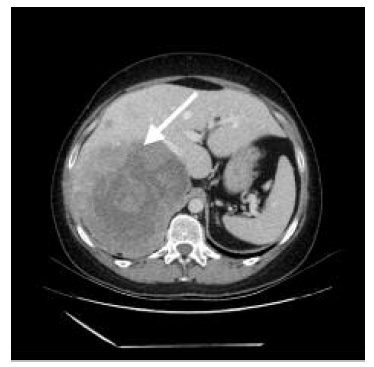

Em janeiro/2023, a utente recorre novamente a consulta com os resultados dos exames. Do estudo efetuado, a destacar MAPA 24 h com “hipertensão arterial sustentada e perfil tensional não dipper”. A ecografia renal apresentava “volumosa massa em íntimo contacto com o bordo posterior do lobo direito hepático medindo cerca de 20 cm de maior eixo incompletamente caracterizada por esta técnica”. A utente trazia já uma tomografia computorizada, que foi realizada imediatamente após a ecografia, e que revelou “no hipocôndrio direito, em relação com o lobo hepático direito, identifica-se volumosa massa heterogénea com áreas de captação na fase arterial e nas fases tardias, demonstrando também algumas áreas hipocaptantes que podem corresponder a áreas necróticas, medindo aproximadamente 16,2 × 14,6 cm de maior eixos axiais e 20,2 cm de eixo longitudinal (...) não se define a glândula suprarrenal pelo que a referida massa pode ter origem suprarrenal ou hepática (...). No segmento hepático VII identificam-se três nódulos hipodensos com 26 mm, 17 mm e 16 mm e no segmento VI um nódulo, cujo comportamento no estudo dinâmico não permite a sua caracterização” (Figuras 1 e 2).

Figura 1 Carcinoma da suprarrenal em tomografia computorizada (corte transversal) - assinalado com seta.